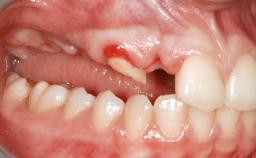

A 20-year-old woman was referred for implant therapy in 2004. Her medical history revealed no significant findings, and neither did she smoke nor take any medications. An extraoral examination revealed no abnormalities of the skin, hair or nails. The intraoral examination revealed only 11 permanent teeth clinically. These were normal in shape, size, and color. In addition, eight retained deciduous teeth (53, 62, 63, 71, 72, 73, 81, 82) were present. No abnormalities were detected during the general examination. The family history revealed that the patient’s father and two sisters were on record with similar conditions. The clinical examination revealed a thick gingival biotype. No recession of the attached gingiva was noted, but the retained deciduous teeth were mobile and unsightly. As a syndrome had not been diagnosed, the case was categorized as non-syndromic oligodontia.

Bone Volume Deficient horizontally, requiring prior grafting